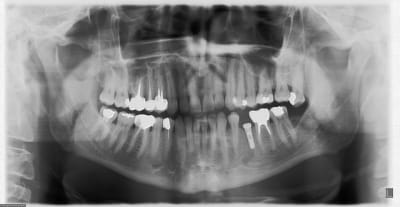

Voici 2 panos avec 2 systèmes différents. Dans un cas c'est une connectique hexagone externe en place depuis 1991 le controle date de 2012.

La 2ème est un controle à 3 ans. Seulement voilà les cas d'os au dessus du col ne sont que trop rarissimes et dans des cas tout à fait exceptionnels. Je pense qu'ils dépendent plus de la qualité de gestion que du matos.